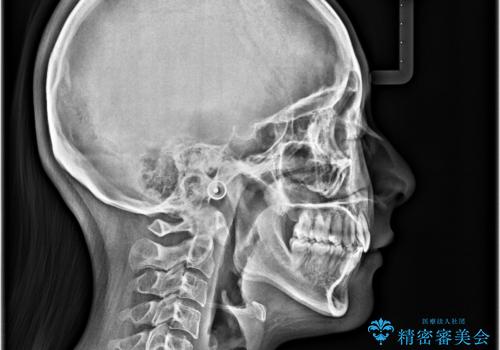

- 前歯部のデコボコと口元が出ているのが気になるとのことで来院された患者様です。

口元の突出感の解消と、このままデコボコを解消するとさらに出っ歯傾向になってしまうことを考慮し、上下左右の小臼歯を抜歯しクリアブラケットにて矯正していくこととしました。

舌突出癖を改善するトレーニングを一生懸命やっていただいたおかげで2年以内に治療を終えることができました。